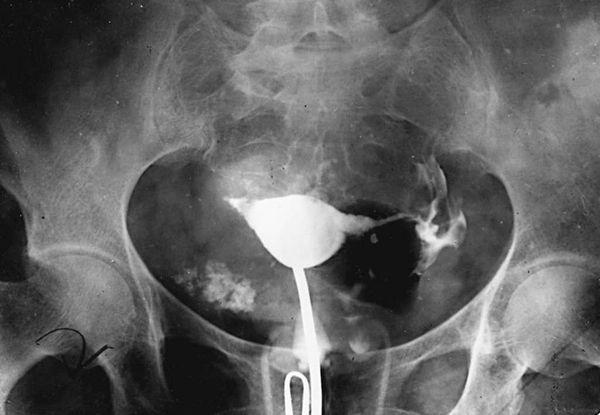

1. Histerosalpingografi (HSG)

Histerosalpingografi (HSG) memanfaatkan teknologi sinar-x real time untuk mengetahui kondisi rahim dan tuba falopi, serta risiko keguguran terkait kelainan pada rahim. Jika terdapat sumbatan pada tuba falopi, dokter juga dapat membukanya melalui pemeriksaan ini.

HSG adalah pemeriksaan pertama yang perlu dilakukan wanita sebelum menjalani tes kesuburan lain. Pasalnya, hasil yang Anda peroleh merupakan dasar untuk melakukan pemeriksaan lanjutan. Terutama bila terdapat gangguan pada organ reproduksi.

Sumber: Fertility Center of San Antonio